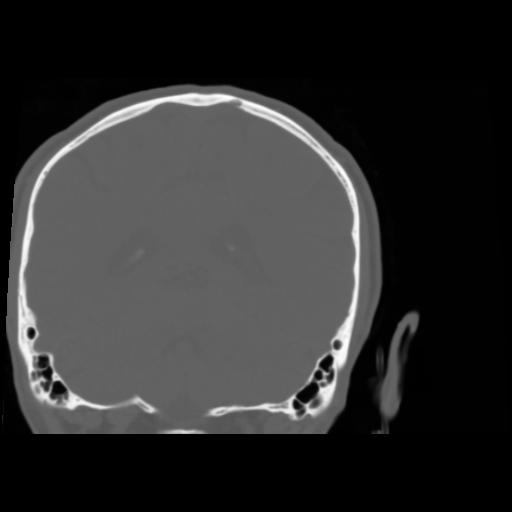

5 CEREBRO,,Coronal,3.000,CEREBRO,Coronal,